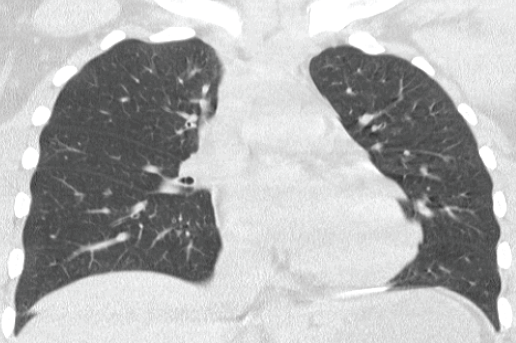

CT of the chest 2 months later showed resolution of the infiltrates and lymphadenopathy (Figure 3). Corticosteroids were tapered over the next month and then stopped. She showed no recurrence of symptoms during a period of one year.

Figure 3. After the young woman’s discontinuation of the inhalant, a high-resolution computed tomography scan of the chest taken 2 months later showed resolution of the subpleural infiltrates and lymphadenopathy.